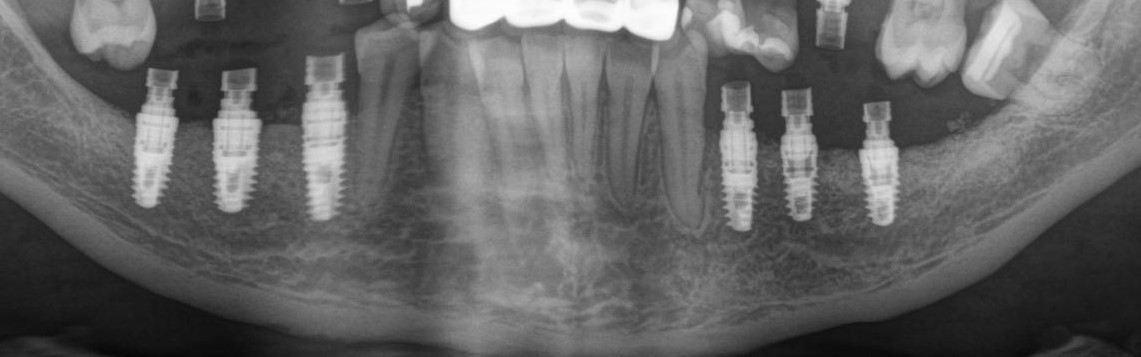

Рентгеновский снимок после операции (расщепление было проведено с двух сторон):

Снимок, сделанный через 5 месяцев после операции:

Обратите внимание, как изменился цвет кости. Она полностью восстановилась. На снимке этот участок стал белее.